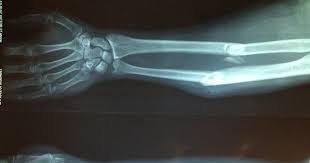

روش جدیدی برای ترمیم استخوان به صورت موضعی

گروهی از محققان دانشگاه مارتین لوتر هاله ویتنبرگ و دانشگاه لایپزیگ آلمان و دانشگاه اویرو پرتغال در جدیدترین مطالعه شان دریافتند روش جدید «Packaged-DNA» می‌تواند به تحریک ترمیم استخوان به صورت موضعی و هدفمند کمک کند.

به گزارش خبرگزاری صدا و سیما: محققان دانشگاه مارتین لوتر هاله ویتنبرگ (MLU) در یک بیانیه مطبوعاتی اعلام کردند که این نوآوری پیشگامانه در حوزه پزشکی می‌تواند پس از یک شکستگی پیچیده یا بعد از دست دادن شدید بافت پس از جراحی مفید باشد. محققان فرآیند جدیدی را توسعه داده‌اند که در آن مواد ایمپلنت را با یک ماده زیستی فعال شده با ژن می‌پوشانند که این امر سلول‌های بنیادی را وادار به تولید بافت استخوانی می‌کند.

استخوان‌ها نمونه جالبی از توانایی بدن برای بازسازی هستند. آن‌ها می‌توانند عملکرد کامل خود را حتی پس از شکستگی به لطف توانایی خود در ایجاد بافت جدید و انعطاف‌پذیری در محل شکستگی به دست آورند. پروفسور «توماس گروت» رئیس گروه تحقیقاتی مواد بیومدیکال از دانشگاه مارتین لوتر هاله ویتنبرگ گفت: وقتی صحبت از شکستگی‌های پیچیده یا از دست دادن بافت بزرگ می‌شود، قدرت خود ترمیمی استخوان کافی نیست. در چنین مواردی، ایمپلنت‌ها برای تثبیت استخوان، جایگزین بخش‌هایی از مفاصل یا رفع نقص‌های بزرگ‌تر با مواد تجزیه‌پذیر مورد نیاز هستند. موفقیت چنین ایمپلنت‌هایی تا حد زیادی به این بستگی دارد که چقدر در استخوان گنجانده شده‌اند. در سال‌های اخیر تلاش‌های زیادی برای حمایت از این فرآیند با پوشش ایمپلنت‌ها با مواد فعال زیستی برای فعال کردن سلول‌های استخوانی و سلول‌های بنیادی مزانشیمی انجام شده است.